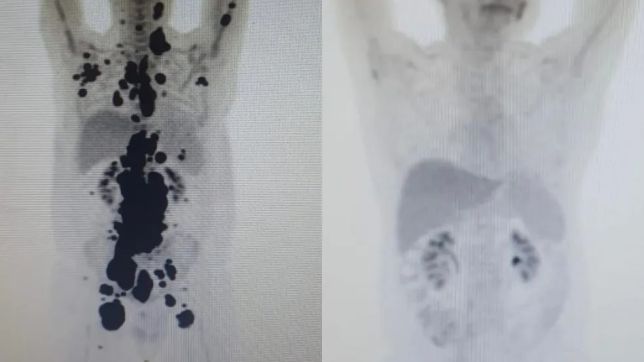

“Foi uma resposta muito rápida e com tanto tumor. Fico até emocionado [ao ver as duas ressonâncias de Paulo]. Fiquei muito surpreso de ver a resposta, porque a gente tem que esperar pelo menos um mês depois da infusão da célula. Quando a gente viu, todo mundo vibrou. Coloquei no grupo de professores titulares da USP e todo mundo impressionado de ver a resposta que ele teve”, comemorou o especialista.

ANTES E DEPOIS

As duas imagens do Pet Scan (tomografia feita com um contraste especial ) (veja acima) representam “dois Paulos”: a da esquerda, o paciente que tinha como caminho único os cuidados paliativos, quando a alternativa é dar conforto, mas já sem expectativa de cura, e a da direita, um paciente com um organismo já sem tumores após o tratamento com CAR-T Cell.

“A vitória não é só minha. É da fé, da ciência e da energia positiva das pessoas. Cada uma delas ajudou a colocar um paralelepípedo nesse caminho. A imagem prova com muita clareza para qualquer pessoa a gravidade do meu linfoma, e eu não tinha ideia de que era assim”, contou o paciente.